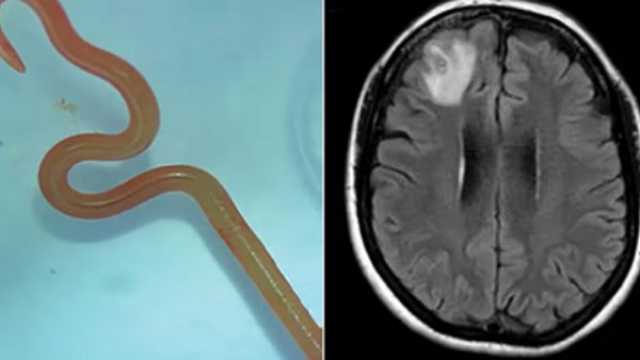

احذر الموبايل.. طالب صيني يصاب بالسكتة الدماغية بسبب الهاتف| تفاصيلبسبب ثعبان نيء.

. دودة حية طولها 18 سم في دماغ رجل صينيفوائد الليمون في إنقاص الوزن